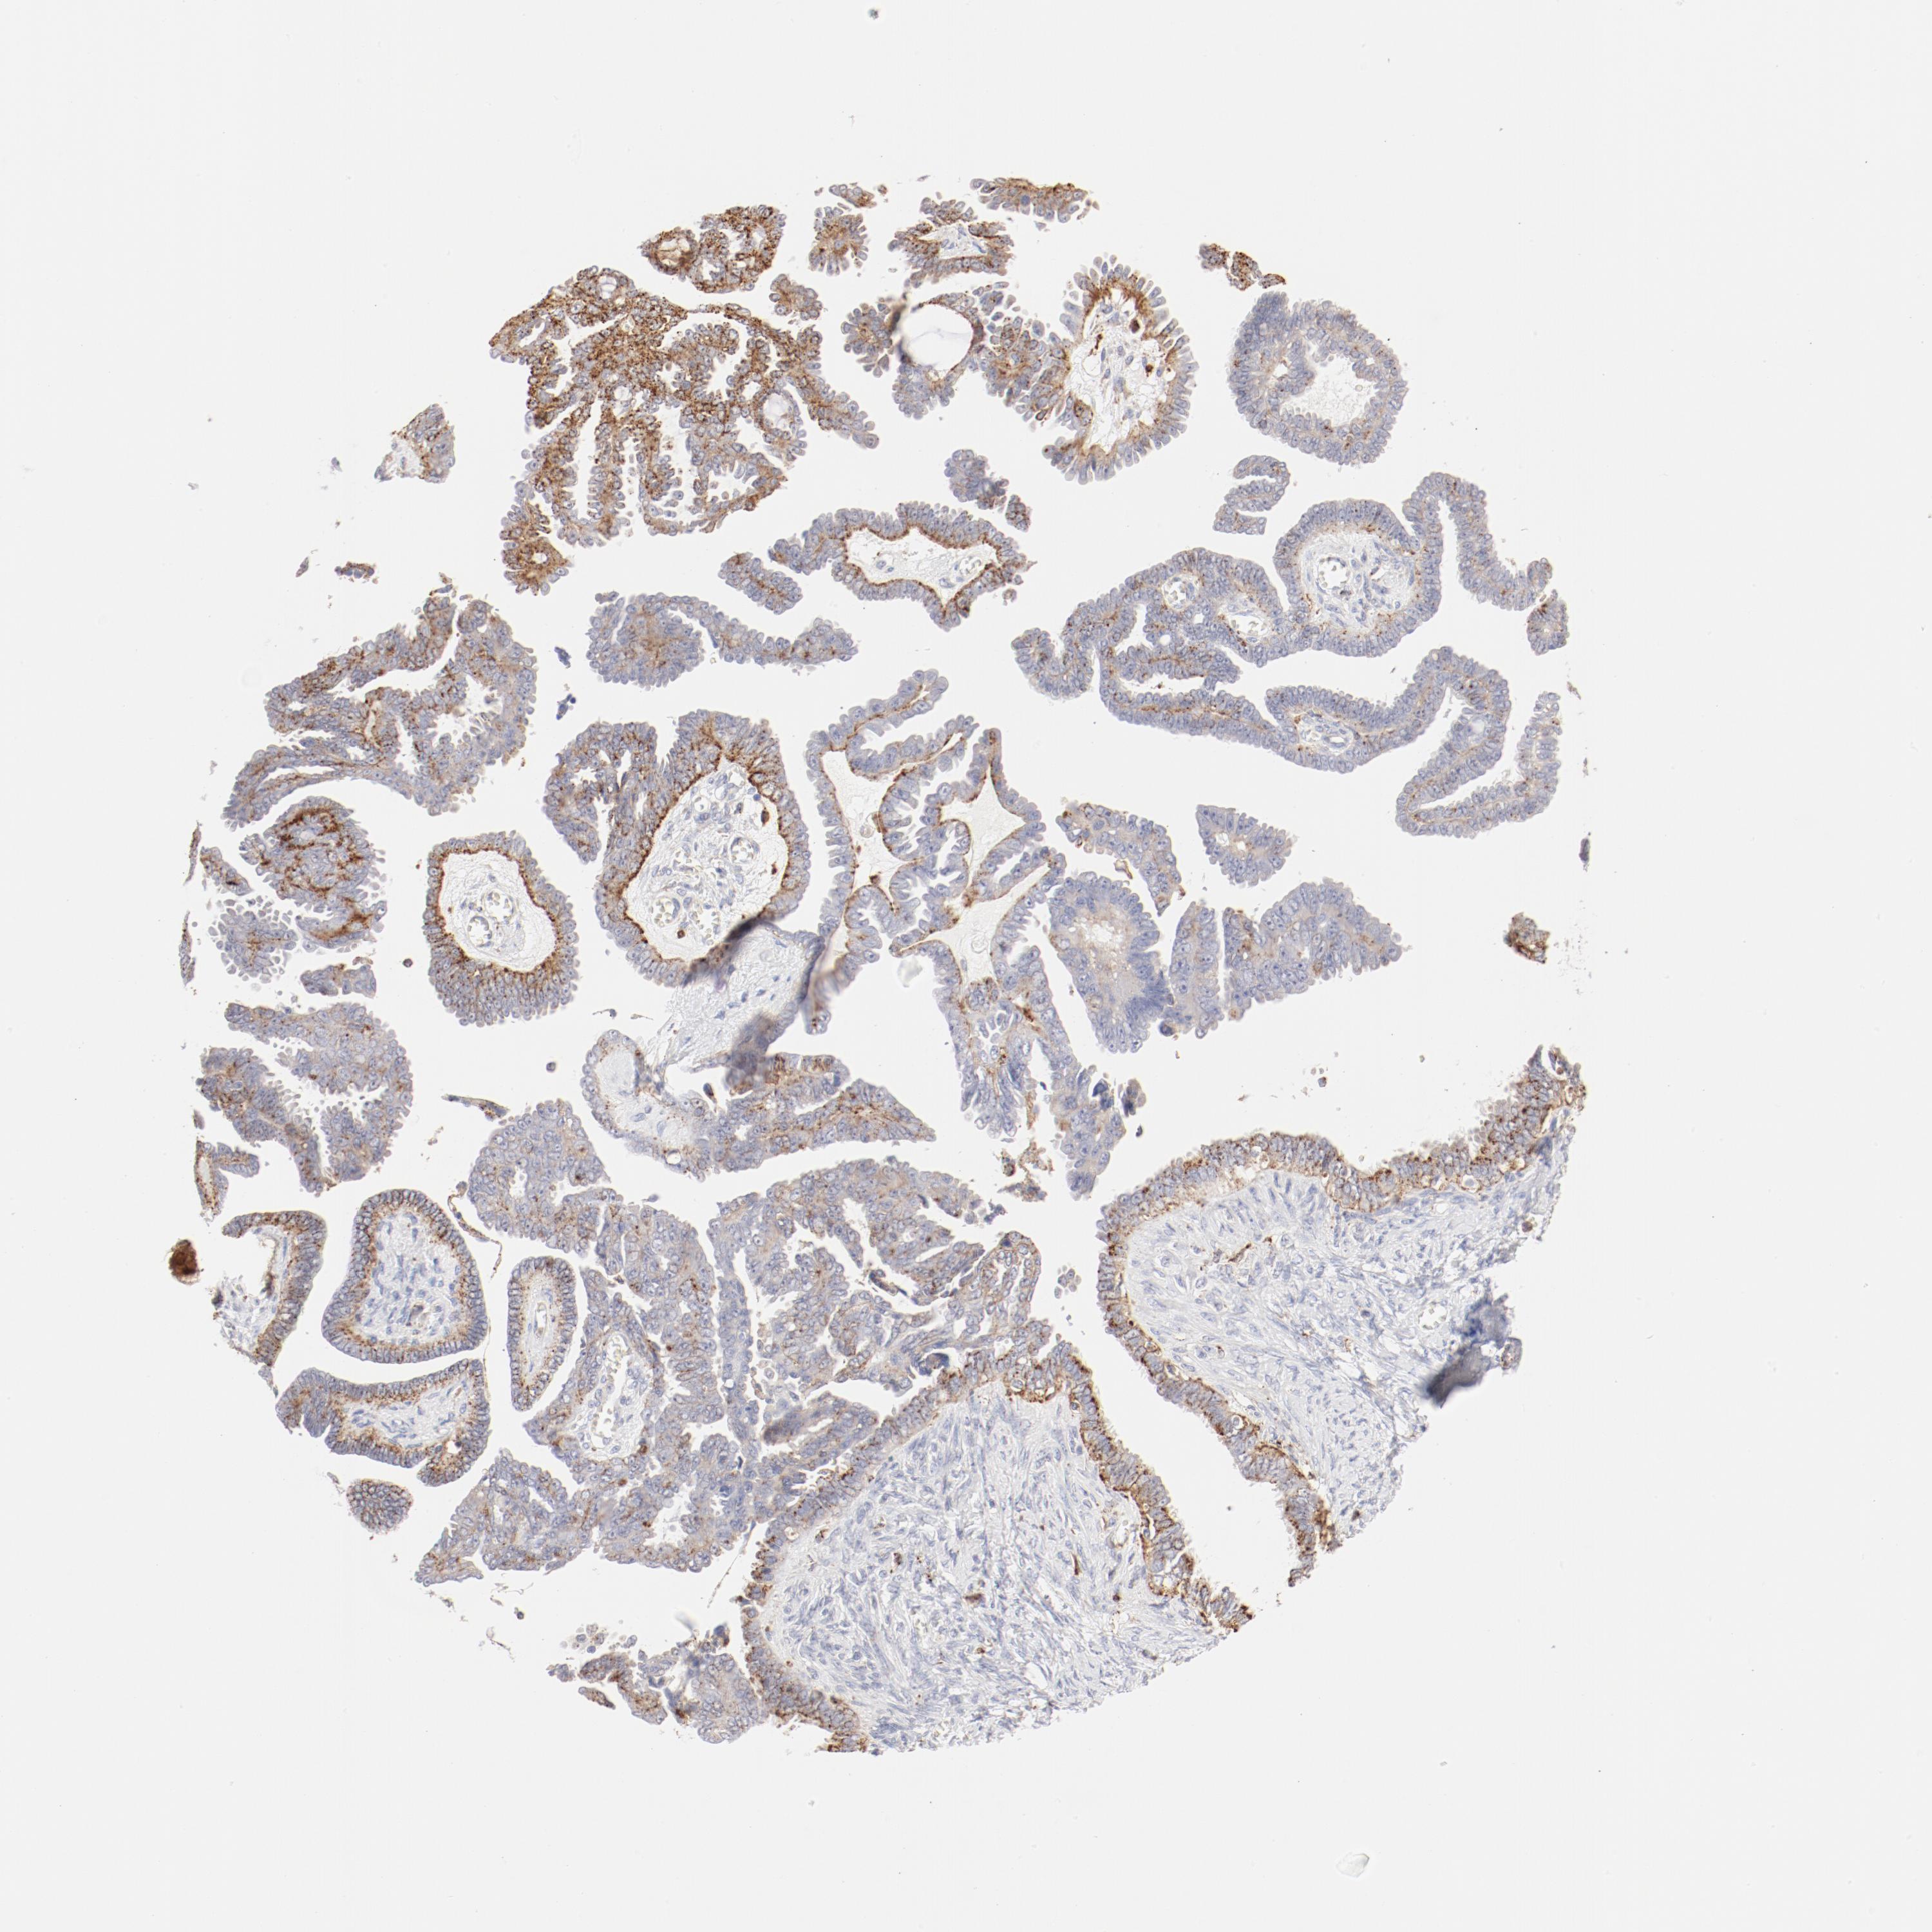

OVARIAN CANCER - Protein expressioni

A mouse-over function shows sample information and annotation data. Click on an image to view it in a full screen mode. Samples can be filtered based on level of antibody staining by selecting one or several of the following categories: high, medium, low and not detected. The assay and annotation is described here.

Note that samples used for immunohistochemistry by the Human Protein Atlas do not correspond to samples in the TCGA dataset.

Antibody stainingi

Antibody staining in the annotated cell types in the current human tissue is reported as not detected, low, medium, or high, based on conventional immunohistochemistry profiling in selected tissues. This score is based on the combination of the staining intensity and fraction of stained cells.

Each image is clickable and will lead to virtual microscopy that enables deeper exploration of all samples and also displays staining intensity scores, fraction scores and subcellular localization as well as patient and tissue information for each sample.

Antibody HPA003524

Antibody CAB000458

Staining

High

Medium

Low

Not detected

Intensity

Strong

Moderate

Weak

Negative

Quantity

>75%

75%-25%

<25%

None

Location

Nuclear

Cytoplasmic/membranous

Cytoplasmic/membranous,nuclear

Cystadenocarcinoma, mucinous, NOS

Carcinoma, endometroid

Cystadenocarcinoma, serous, NOS